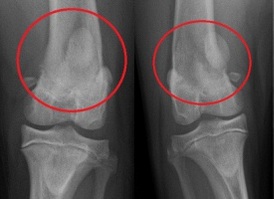

Knie     Kniescheibe ist herausgesprungen

beim Mensch     Kniescheibe ist herausgesprungen

und ist an der Seite, Röntgenfoto bei

einem Hund    Schema Knie Querschnitt

"Herausgesprungene" Kniescheibe (lat.: Platella-Luxation)

Kniescheibe ist herausgesprungen

beim Mensch

Kniescheibe ist herausgesprungen beim Mensch [4]

-- die instabile Kniescheibe [mit zu flacher Rinne] springt oft beim Sport heraus bei einer "Verdrehung des Knies" (Patella-Luxation) [web01]. Bei einer instabilen Kniescheibe reicht eine leichte Verdrehung des Knies - z.B. beim Sport - und die Kniescheibe fliegt raus [web05 (1'29''-1'36'')], oder auch bei einem Unfall kann eine instabile Kniescheibe herausspringen [web06 (20''-28''9]

-- wenn die Kniescheibe an der Unterseite oder die Rinne verformt sind und nicht mehr reibungslos gleitet, drückt die Kniescheibe von aussen gegen die Rinne, und im Extremfall kann die Kniescheibe aus der Rinne herausspringen [web04]

-- weitere Faktoren für das Herausspringen der Kniescheibe sind auch schlecht arbeitende Muskeln und Sehnen der Kniescheibe [web04]

-- "herausgesprungene" Kniescheiben kommen in jedem Alter vor [web04], vor allem aber bei Mädchen und jungen Frauen [web02], anatomisch begünstigt mit X-Beinen und anderen Bein-Fehlstellungen [web01]